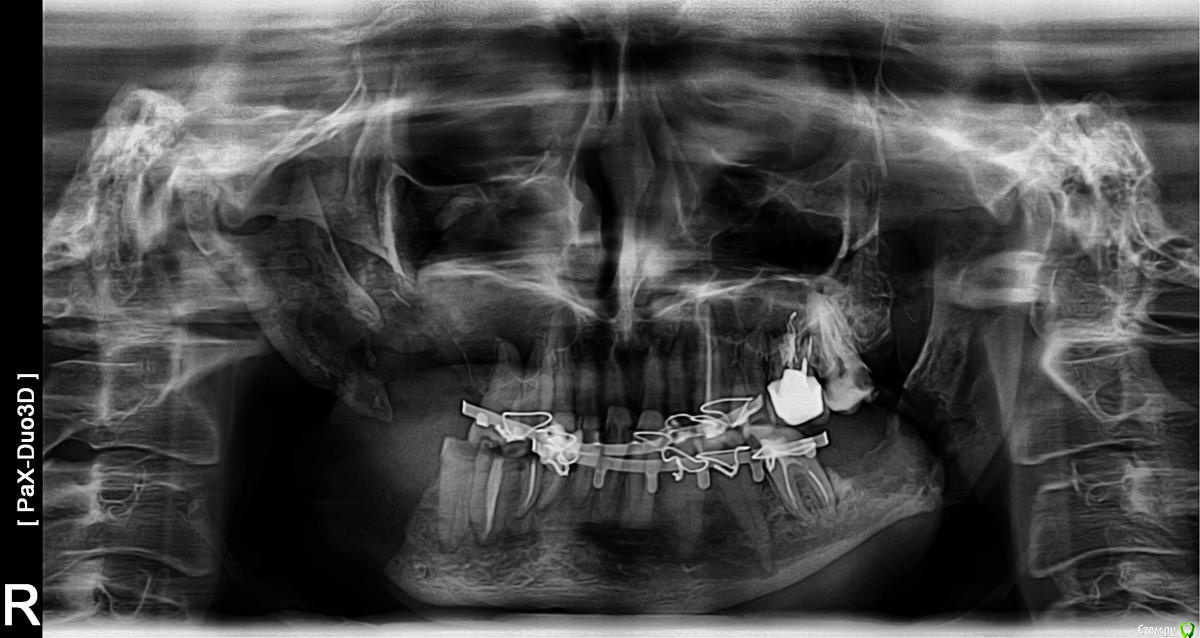

venedy2 Опубликовано 23 марта, 2016 Поделиться Опубликовано 23 марта, 2016 Добрый день, надеюсь поможете советом.В ноябре 2009 году был поставлен диагноз - недефференцированный рак носоглотки справа T4N1M0. прошел 8 курсов химиотерапии в НИИ им.Герцена (таксотер+доксирубицин+цисплатит) и 65 грей облучения( 45-шея и 65-носоглотка), операцию по удалению лимфоузлов врачи решили не проводить.Лечение завершено 16.07.2010.После облучения рот стал открываться хуже, но не критично,челюсть сместилась вправо. 12 октября 2010 появились боли в челюсти справа-оказалось зуб мудрости начал лезть и толкать остальные зубы, была проведена операция по его удалению (вскрывали десну, выпиливали зуб, 7 дней антибиотики, 14 дней стационара).В начале ноября 2011 я зевнул и сломал челюсть (в месте удаления зуба мудрости и соответственно месте облучения), в челюстно-лицевой хирургии по месту жительства(г.Тула) сказали -"ничего делать не будем,не ешь, не пей, не говори - срастется когда нибудь". Не успокоившись на этом ответе я поехал в Герцена, сделали рентген - перелом есть, онкологии нет,и направили в Стоматологический комплекс на Вутетича 9а (г.Москва). Но так как в очередной раз я ухитрился подхватить сильнейший гайморит, то обращении туда пришлось отложить до 2012г.Сейчас я прошел контрольное обследование в Герцена(18.01.2012), все в порядке, признаков опухоли, метастаз, некроза нет (только перелом который чуть сместился и отсутствие признаков консолидации), меня перевели на режим обследования раз в полгода и вновь дали направление в Стоматологический комплекс (мотивируя тем, что их специалисты присутствуют на операциях в Герцена). Попал сегодня на консультацию профессора удалено администратором и доцента удалено администратором которые первым делом спросили почемы вы пришли именно к нам,вторым назвали диски с записью рентгена и КТ "фантиками,что ты нам их показываешь", а затем отказали в какой либо операции мотивируя это тем, что при вмешательстве сразу же начнется некроз тканей или же вернется опухоль, и что необходимо удалять половину челюсти с заменой на имплантант (хотя в герцена хирург говорил лишь о пластине в месте перелома), в консультативном заключении написано:Диагноз: патологический перелом н.челюсти справаРекомендации:Больной проконсультирован проф. удалено администратором. Учитывая воспалительный инфильтрат и ранее проведенной лечение (курс лучевой и ПХТ) не(зачеркнуто) представляется возможным(зачеркнуто) нецелесообразным.Rg-снимки выданы на руки.В итоге взялись за мени в НМХЦ им. Пирогова. Перенес около 6 операций с 2012 по 2014 гг. (ставили титановую пластину- нагноилась убрали - снова ставили - снова убрали - закрыли деффект мышечным лоскутом с шеи).Постоянно свищ с выделением. В июне 2015г. вытащили осколок кости, все заросло. Был конечно лица дефект заметен - но есть можно, говорить нормально, ходил в спортзал, набрал вес. В декабре 2015 начал болеть зуб мудрости слева - пришлось удалять его и 7ку там же + 5,6 зубы на верхней челюсти справа(сильно разрушены были). Итог - на месте удаления в нижней челюсти начался остеомиелит, в феврале под общим наркозом чистка, во время операции челюсть сломалась. Месяц в шинах - сращения обломков нет. Хожу пока так. Прикрепляю ОПГ.Вопросы следующие :1. Куда можно обратиться с подобной проблематикой в России?2.Что вы скажете про эндопротезирование никелидом титана?3.Какие есть вообще варианты? Ссылка на комментарий

venedy2 Опубликовано 27 марта, 2016 Автор Поделиться Опубликовано 27 марта, 2016 Вчера место перелома начало болеть, сделал КТ челюсти. Ссылка на комментарий